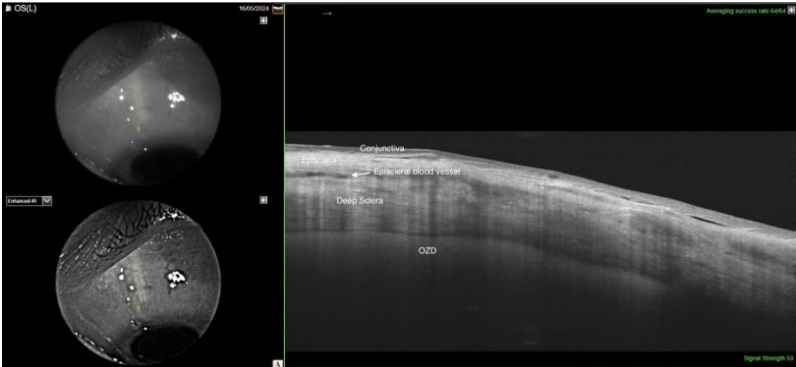

技术方法上,研究采用3D头戴式显示系统(NGENUITY)辅助手术,通过睫状体平坦部3-4mm处的放射状巩膜切口建立脉络膜上腔通路,配合粘弹剂分离空间后植入药物。术后通过扫频OCT(DRI OCT)验证植入位置,主要评估中央视网膜厚度(CRT)、最佳矫正视力(BCVA)和眼压(IOP)变化。

3)地塞米松较曲安奈德具有6-7倍更强效价。值得注意的是,术后10个月随访未观察到植入物降解相关并发症,扫频OCT显示植入物稳定位于锯齿缘附近(

这项研究为复杂CME的治疗开辟了新途径,特别是对Yamane技术等悬吊式人工晶状体植入日益普及的现状具有重要临床意义。研究者同时强调,该技术的长期效果仍需更大样本的前瞻性研究验证,但其展现的"解剖结构适应性治疗"理念,或将为其他眼部给药系统设计提供新思路。